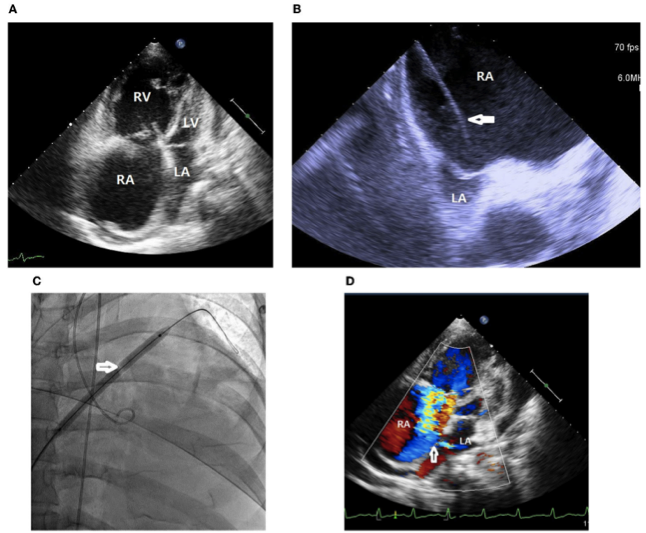

一名患有IPAH的37岁女性,接受了最大程度的靶向药物治疗,包括口服5型磷酸二酯酶抑制剂、内皮素受体拮抗剂和皮下注射PA(曲前列尼)。除IPAH外,患者没有显著的既往病史。2020年4月,患者出现右心衰恶化,伴有外周水肿、少尿和低血压。入院时,收缩压为92/76 mmHg,脉搏为107次/分钟,在室内空气中脉搏血氧饱和度为91%,呼吸频率为20次/分钟。体检显示颈静脉巨大V波,估计中心静脉压≥20 cmH2O,II级全收缩期杂音,左胸骨下缘可触及隆起。实验室数据显示贫血,血红蛋白7.8 g/dL,低钾血症3.0 mEq/L,NT-pro-BNP升高4138 g/dL。经胸超声心动图显示RA和右心室(RV)明显扩张,此外还有小而受压的左心房(LA)和左心室(LV)(图1A)。

通过外周中心静脉导管(PICC)将皮下注射转为静脉注射PA,并登记在肺移植等待名单上。入院第7天,进行了标准的左、右心导管检查。基线平均RA压力为14 mmHg,经鼻导管供氧3 L/min的情况下,主动脉血氧饱和度为96%,全身CO为2.9 L/min,全身OD为291 cc/min。将心内超声心动图(ICE)导管经左股静脉引入RA,图像显示在ACUSON SC 2000系统上。使用实时ICE引导,房间隔和卵圆窝清晰可见。在进入LA腔之前,使用跨室间隔Brockenbrough针和Mullins鞘在ICE引导下进入LA腔之前探测房间隔(图1B)。随后用5 mm×8 cm和6 mm×8 cm的Mustang球囊扩张房间隔(图1C)。BAS后,全身CO增加到3.5 L/min,OD增加到318 mL/min,而全身动脉血氧饱和度下降到87%(鼻导管下 3 L/min供氧)。然而,没有观察到RA压力立即下降。经胸超声心动图证实建立了从右到左的心房分流(图1D)。在BAS联合持续静脉输注PA后,患者的心力衰竭症状缓解至功能II。此后,症状保持稳定。

图1. (A)经胸超声心动图显示右心房和右心室明显扩张,左心房和左心室小而压缩。(B)心内超声心动图显示右心房明显扩张,左心房小而受压。经中隔Brockenbrough针和Mullins鞘(白色箭头)用帐篷征探测房间隔。(C)用6 mm×8 cm的球囊(白色箭头)扩张房间隔。(D)经胸超声心动图证实建立了从右向左的心房间分流(白色箭头)。RA,右心房;RV,右心室;LA,左心房;LV,左心室